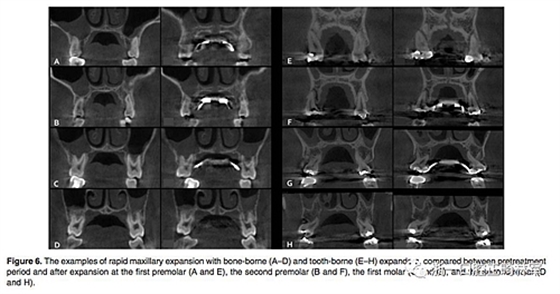

(1)牙支持式和骨支持式快擴(kuò)之間的比較(Figure 6,Table 1)

骨骼變化:腭中縫線在兩組中都以三角形模式被成功打開(kāi),鼻底增加最少,硬腭以下5mm平面出被打開(kāi)最多(P<0.001)。骨骼的擴(kuò)張比牙齒的水平要少。除了第一前磨牙區(qū)域的線性測(cè)量值外,骨支持式組顯示擴(kuò)張程度比牙支持式組顯著增加。

牙性變化:兩組的牙槽骨和牙長(zhǎng)軸的角度變化都很明顯。牙支持式組在全部區(qū)域都顯示出比骨支持式組更大的頰側(cè)傾斜(P<0.01)。牙支持式組的牙槽骨頰傾更明顯,第二磨牙區(qū)域除外(P <0.05)。在第一前磨牙和第一磨牙,兩組在根尖處的橫向距離增加是相似的。然而,在第二前磨牙和第二磨牙中,牙支持式組發(fā)生根尖橫向距離增加較少。在牙冠水平,僅在第二前磨牙處,兩組之間的擴(kuò)張相似。牙支持式組在第一前磨牙和第一磨牙產(chǎn)生更多的牙冠之間橫向距離增加,而骨支持式更多發(fā)生在第二磨牙。在第一前磨牙和第一磨牙的垂直向變化方面,兩組之間沒(méi)有區(qū)別。 第二前磨牙區(qū)頰尖頰傾和腭尖掛下在牙支持式組比骨支持式組更明顯(P <0.05)。在第二磨牙區(qū)域,僅在頰尖頰傾方面兩組有統(tǒng)計(jì)學(xué)差異(P <0.05)。除了第一前磨牙在牙支持式組的頰側(cè)骨開(kāi)裂明顯(P <0.01)之外,兩組間垂直牙槽骨損失量沒(méi)有顯著差異。